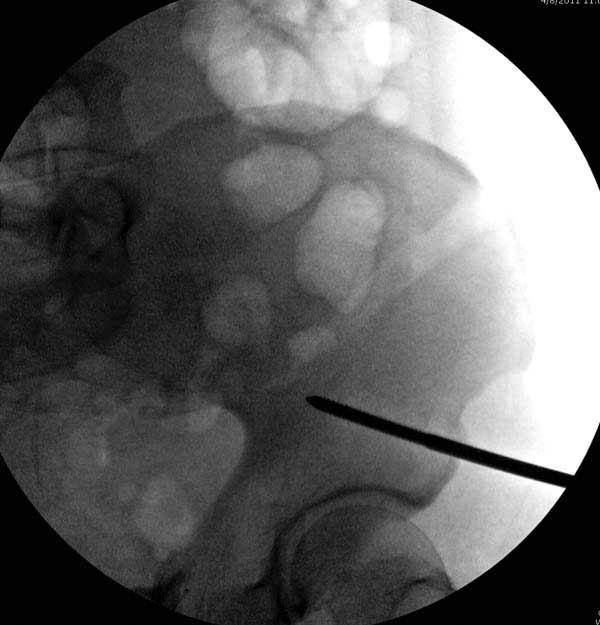

Здесь представлен случай 38 летнего больного (падение с высоты 9 метров) с нарушением тазового кольца. При поступлении для стабилизации передне-нижний аппарат наружной фиксации и на 6й день, вчера, операция из двух доступов.

Представлены снимки техники проведения стержней. Через место прикрепления прямой мышцы в Inferior Iliac Spine в направления вырезки создается жесткость. Weber clamp изнутри таза для репозиции, и фиксация после репозиции перелома крыла подвздошной кости. Наружный аппарат удален, нагрузка предполагается через два месяца.